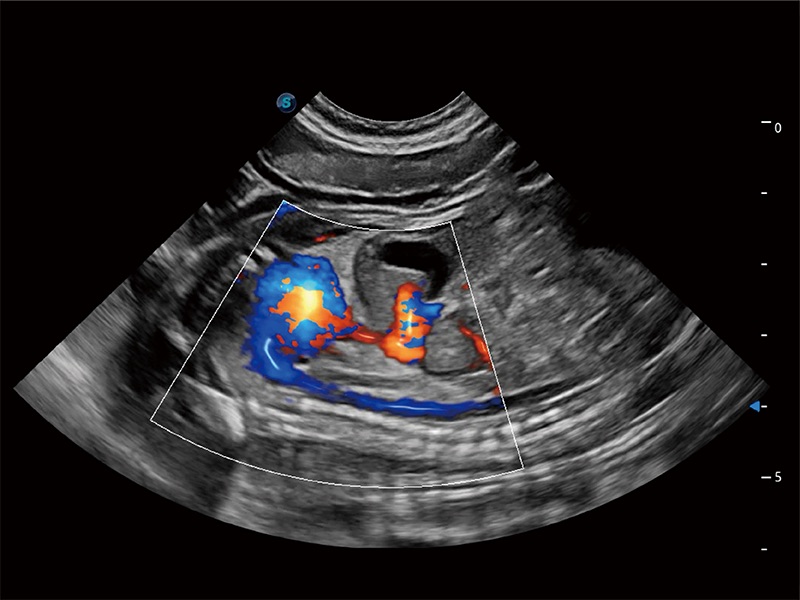

极大提升超低速微细血流的检出能力,同时更精准地滤除软组织和超声信号,为兽用医生提供以往无法通过常规血流获得的疾病诊断信息。

在传统二维血流成像的基础上,呈现血流的立体感,具有动感的生命力之美。即便是微小的血管也能轻松应对,提高了血流的视觉敏感性。

非线性融合造影成像充分利用谐波和基波信号,为难以观察的血流进行增强显像。可用于线阵、凸阵、微凸阵、相控阵探头。